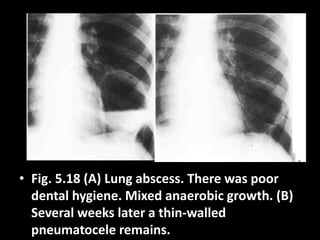

• Fig. 5.18 (A) Lung abscess. There was poor

dental hygiene. Mixed anaerobic growth. (B)

Several weeks later a thin-walled

pneumatocele remains.

• Fig. 5.18(A) Lung abscess. There was poor dental hygiene. Mixed anaerobic growth. (B) Several weeks later a thin-walled pneumatocele remains.